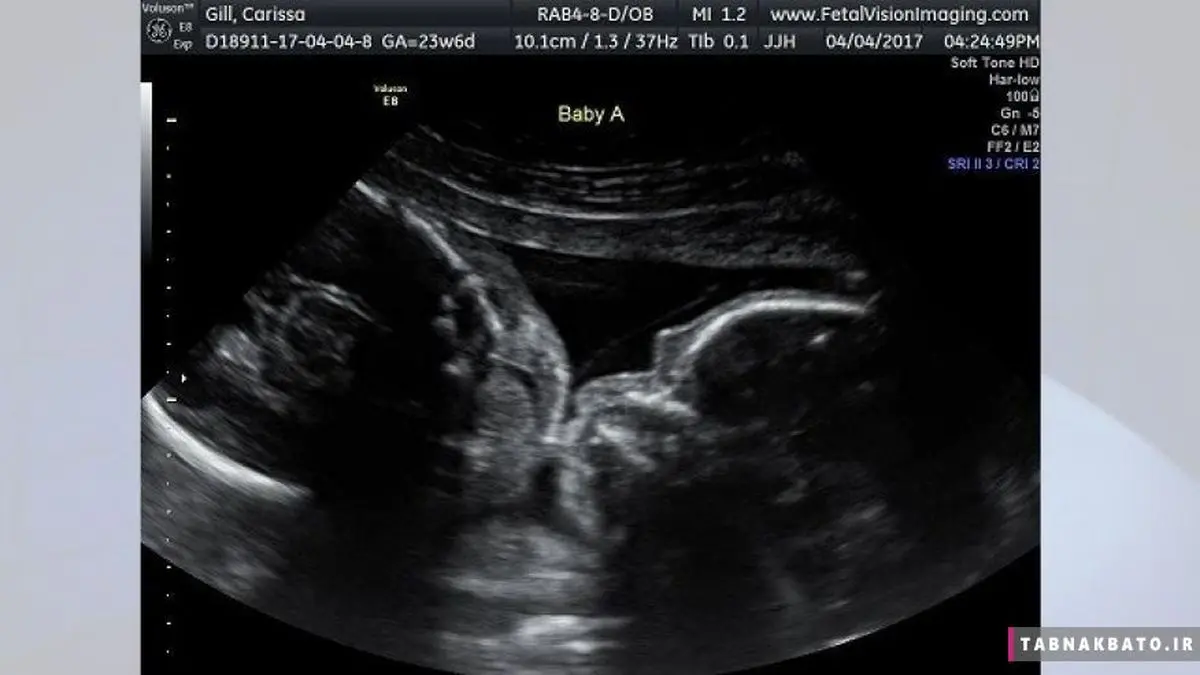

کاریسا جیل (Carissa Gill)، یک زن اهل کرویدون (شهری در جنوب لندن) که در هفته بیست و چهارم بارداری دوقلوهای خود است، یک لحظه‎ی خاص و جالب توجه را در روز سه‌شنبه همراه با همسرش به اشتراک گذاشت. این زوج در زمان حضور خود در مرکز تصویربرداری از جنین شهر لویتون (Levittown)، از این تصویر جالب رونمایی کردند.

وقتی نوبت به سونوگرافی کاریسا در این مرکز تصویربرداری از جنین رسید، این زوج، شاهد صحنه‌ای غیر عادی بودند. دوقلوهای یکسان آنها، ایزابل و کالی، یکدیگر را در آغوش گرفته بودند و به نظر می‌آمد که در حال بوسیدن همدیگر هستند.

کاریسا در مصاحبه با «فاکس 29»، گفت: من دوست داشتم تا این ماجرای لذت‌بخش و زیبا را با جهان به اشتراک بگذارم. عکس‌های بارداری، بهترین عکس‌های یادگاری هستند، مخصوصاً زمانی که شما شاهد چنین لحظاتی باشید.